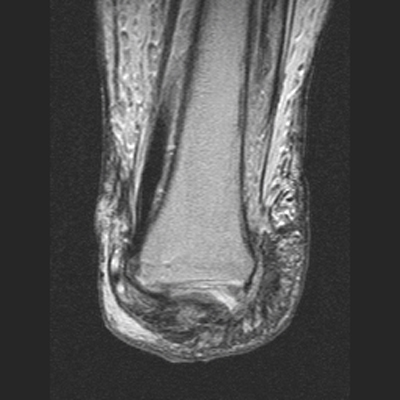

The MRI images below demonstrate the level of the Symes amputation along with bony and

soft tissue changes. Note the thick heel pad forming the majority of the distal

stump: the principle advantage of this procedure due to the more effective weight bearing.